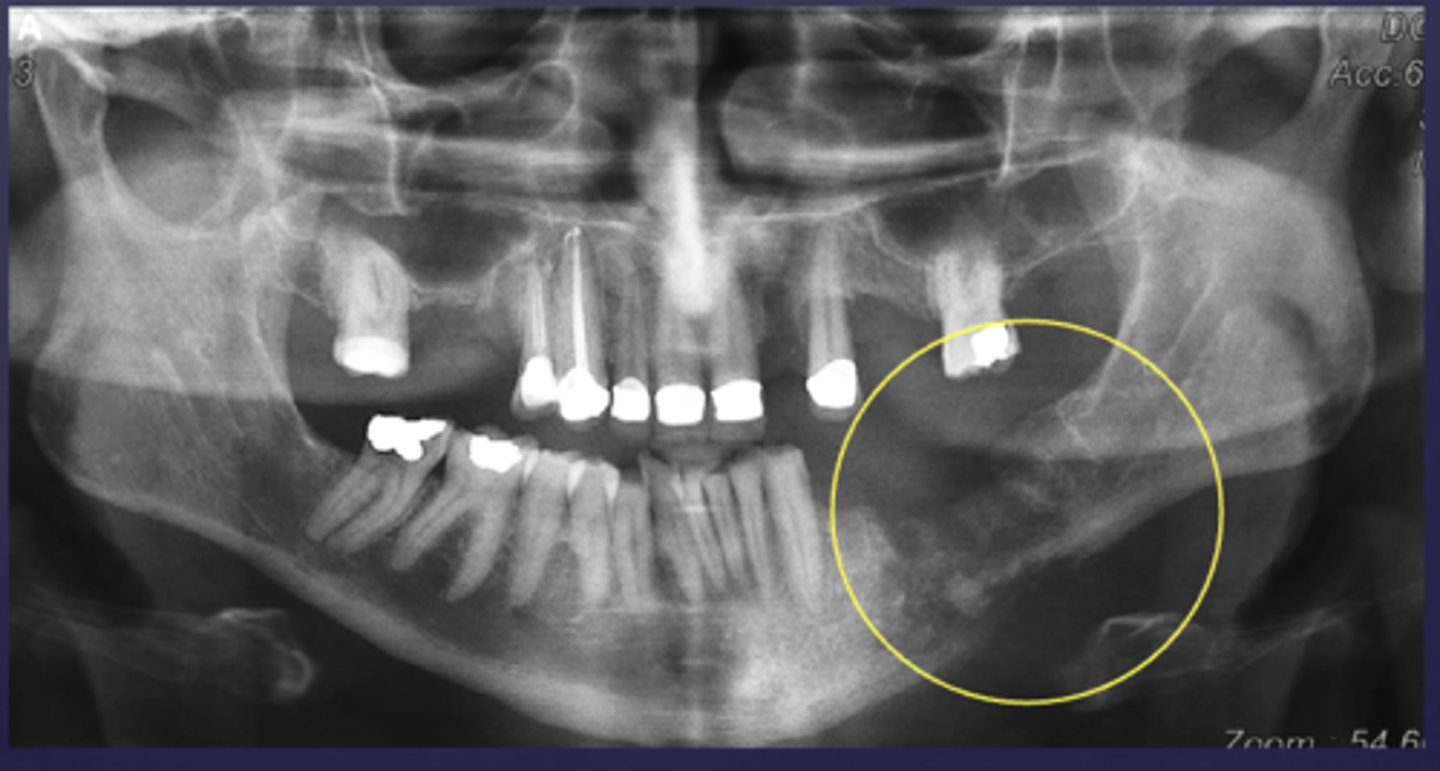

What is the differential diagnosis of the left angle-ramus of mandible?

diffuse sclerosing osteomyelitis (chronic osteomyelitis)

A patient's pano is shown and presents with wrist symptoms. What is the differential diagnosis?

SAPHO Syndrome